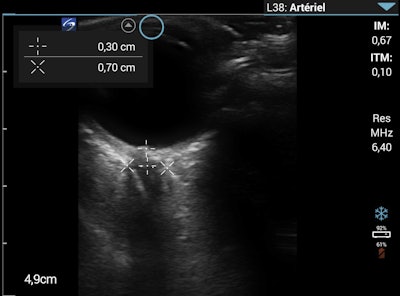

That evening in Dingboche, the patient, a physician himself, was alert, oriented, and showed no signs of ataxia with tandem gait. Lung auscultation was normal, with an absence of inspiratory crackles. Lung ultrasound, however, showed one to two B-lines in four of the four lung regions. The ONSD measurement remained unchanged at 6 mm.

At breakfast, he did not have a cough or a fever. He was mildly ataxic with tandem gait but had normal mental status without other neurologic findings. On lung ultrasound, the number of B-lines in all regions had increased compared with the previous evening and the ONSD had increased to 7 mm.

These are the details of events Wipplinger and colleagues described in a case report published March 17 in Wilderness and Environmental Medicine. She and her colleagues were part of a high-altitude medical research expedition that had started in Lukla at about 9,400 feet. They were equipped with handheld point-of-care ultrasound (POCUS) machines that allowed them to test (with the unfortunate help of the patient) the potential of POCUS to diagnose acute high-altitude illness by lung ultrasound (LUS), optic nerve sheath diameter (ONSD) measurement, and echocardiography.